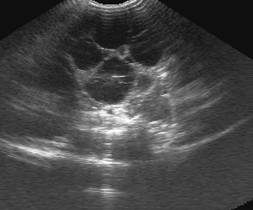

Кисти нирок

Прості кисти нирок, як правило, є

випадковими знахідками. Вони виявляються при ультразвуковому обстеженні як

поодинокі, круглі, ехонегативні утворення з дистальним підсиленням, що

викликане підвищеною звуковою трансмісією. Складні кисти можуть мати ехогенні

перетинки або уламки.

Рис. 2. Проста киста правої нирки

(стрілка) у кота 2 років

Полікистоз нирок

Назва - полікистоз нирок - дає уяву

про його сутність і дослівно перекладається як наявність множинних порожнин в

структурі нирки. Полікистоз нирок є аутосомально домінантним спадковим

захворюванням.

Рис.3. Полікистоз правої кирки кота

4 років, фрагменти сканограм

Розміри кист можуть коливатися від 1

мм до 1 см і більше. З віком їх розмір і кількість збільщуються аж до повного

заміщення нормальної структури нирки різнокаліберними порожнинами. Досить часто

аналогічні кисти можливо виявити в ураженої полікистозом тварини і в інших

органах - підшлунковій залозі, печінці, матці. По мірі прогресування

захворювання і порушення нормальної структури нирок не може не знизитися їх

функція. Зниження функції нирок характеризується хронічною нирковою

недостатністю, що, як правило, є першим тривожним симптомом цього захворювання.